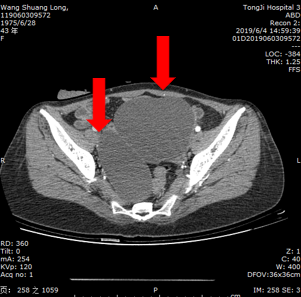

2019.6.4复查CT

降结肠病灶较前大致相仿;

盆腔巨大囊性占位性,较前增大;

总体评价为SD。

影像学检查:

2019.6.4盆腔CT